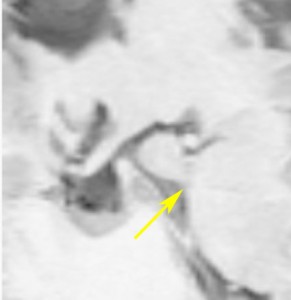

小さな典型的な視床下部過誤腫

無症候で発見されたpedunculated typeです。視床下部の底面からぶら下がるようにしてあります。左のCISS画像で形がよくわかります。中央のT1では灰白質と等信号です。右のT2では高信号となっています。

乳頭体(矢印)からは離れているタイプです。ですから笑い発作を生じません。右側のガドリニウム増強画像ではまったく増強されていないのが特徴です。